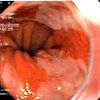

Хромоскопия пищевода и желудка

Хромоскопия пищевода и желудка – методика окрашивания тканей при эндоскопии, дополняющая и расширяющая возможности эндоскопической диагностики. Всего в Саратове найдена 1 клиника, где можно сделать хромоскопию пищевода и желудка.